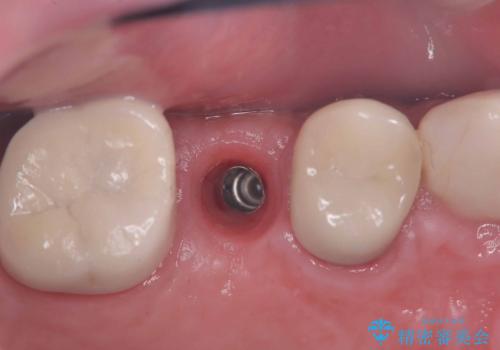

痛く無いインプラント治療!|残根状態の治療

- 被せ物が外れたを主訴に来院された患者様です。

診査の結果保存困難だったので、抜歯後インプラント治療を行いました。

当院では、インプラント治療に際し、痛みの少ない治療を心がけております。

インプラント手術後、痛みが無かったことに患者様も大変驚かれ、治療にご満足いただけました。